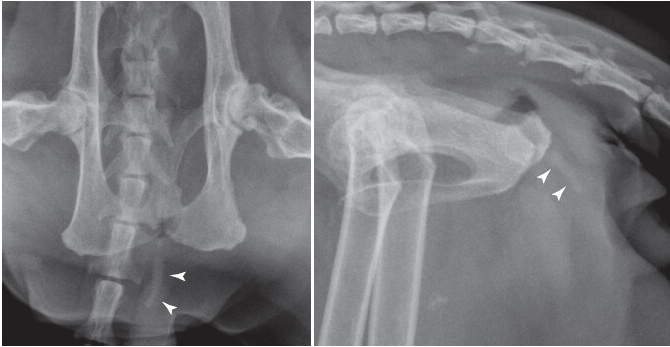

What is this?

Urethral plug/obstruction in a male cat